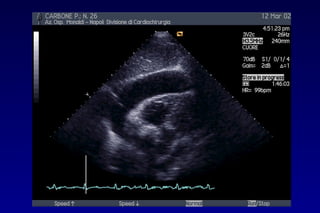

METODOLOGIA DI STUDIOMETODOLOGIA DI STUDIO PITFALLSPITFALLS

METODOLOGIA DI STUDIO DELMETODOLOGIA DI STUDIO DEL

VERSAMENTO PERICARDICO:VERSAMENTO PERICARDICO: PITFALLSPITFALLS

Linfoma mediastinico

Valutazione quantitativa? CT?

Valutazione quantitativa?

ETE?

Utile nello studio di versamenti pericardici saccati.